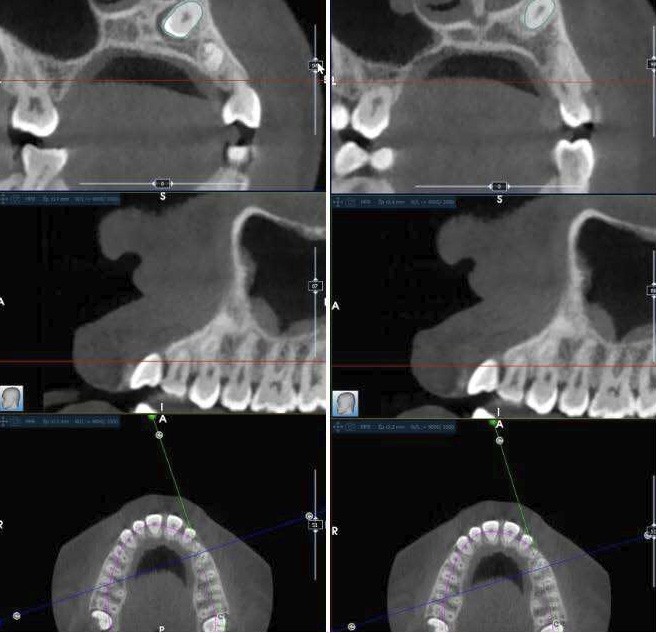

Diagnostic (fig. 1 et 2)

La radiographie panoramique permet de confirmer l’inclusion de la 23, apicale aux dents 21 et 22, ainsi que la présence d’un odontome en apical de la 63. Ces éléments nécessitent la réalisation d’un CBCT.

Le CBCT révèle une position très apicale de la 23. L’apex est fermé.

La téléradiographie de profil montre une Classe II squelettique par biprognathie, avec proalvéolie et vestibuloversion de l’incisive mandibulaire.